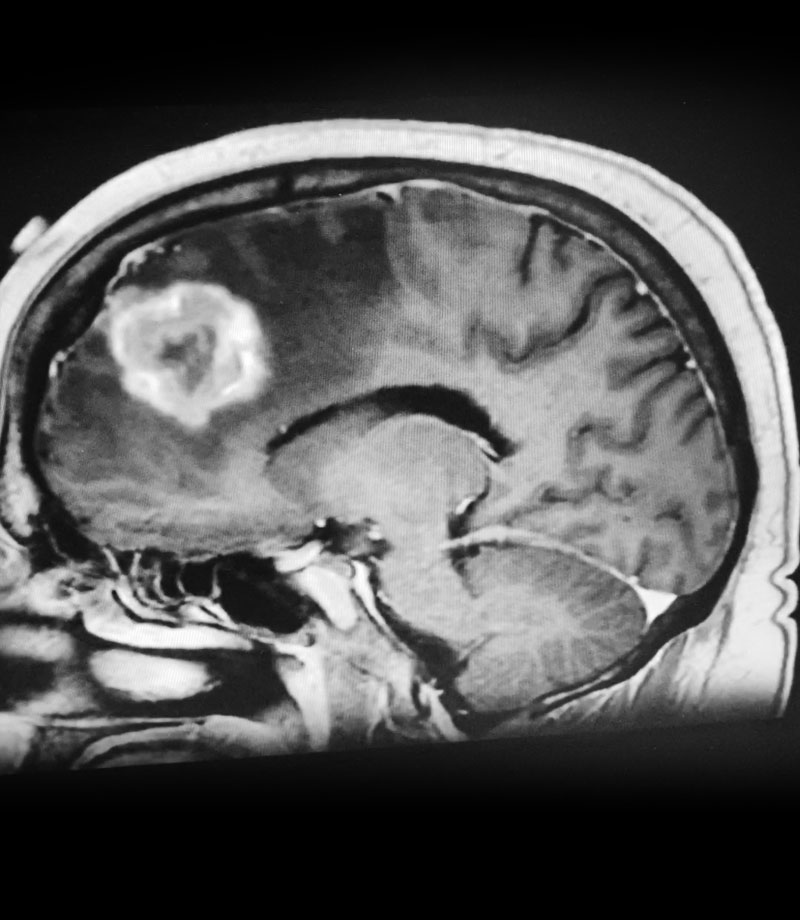

Figure 2: Axial post-contrast MRI.

The patient subsequently had increased headaches and weakness. MRI showed the mass had increased further, with persistent surrounding edema (Figure 1). Systemic work-up showed no active metastatic disease. It was suspected that there was recurrence of metastatic tumor as well as some component of necrosis (Figure 2). The patient underwent a right frontal craniotomy, by Dr. Michael Brisman, with brainlab stereotactic guidance. A cortical incision was made right over the mass. The mass was consistent primarily with metastatic tumor. The tumor was surgically removed.